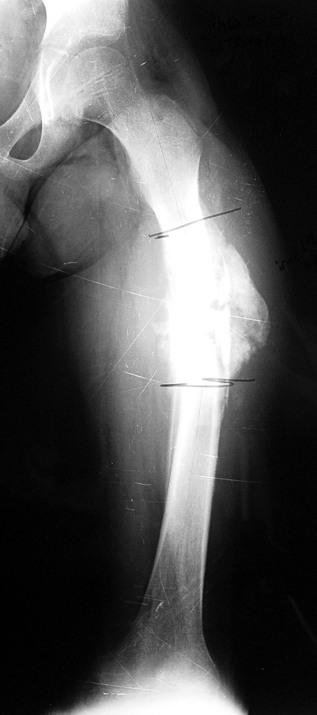

Appropriate radical debridement necessitates excision of all necrotic bone and soft tissues, and frequently causes instability at the involved extremity. The remaining bone and soft tissue defect has to be fixed and reconstructed. The distraction osteogenesis method of Ilizarov is used successfully for achievement of union, correction of the deformity, elimination of limb length inequality and reconstruction of segmental bone defects.

The duration of external fixation (external fixation index) depends on the amount of distraction required, and the extremity is prone to complications during this period. After the distraction phase is completed, the external fixator remains in place during the consolidation phase, which lasts twice as long as the distraction phase; but this period is hardly tolerated. If the external fixator is removed before sufficient consolidation is achieved, fractures, deformity and shortness will be the result. In our department, ‘lenghthening over nail’ method is used in order to decrease the external fixation index and increase patient comfort and activity level. In this method, the intramedullary nail is statically locked after the completion of the distraction phase, and external fixator is removed. The extremity is stabilized by the intramedullary nail during consolidation phase. In this way, complications due to long external fixation index or early removal of the external fixator are avoided.

Case 3